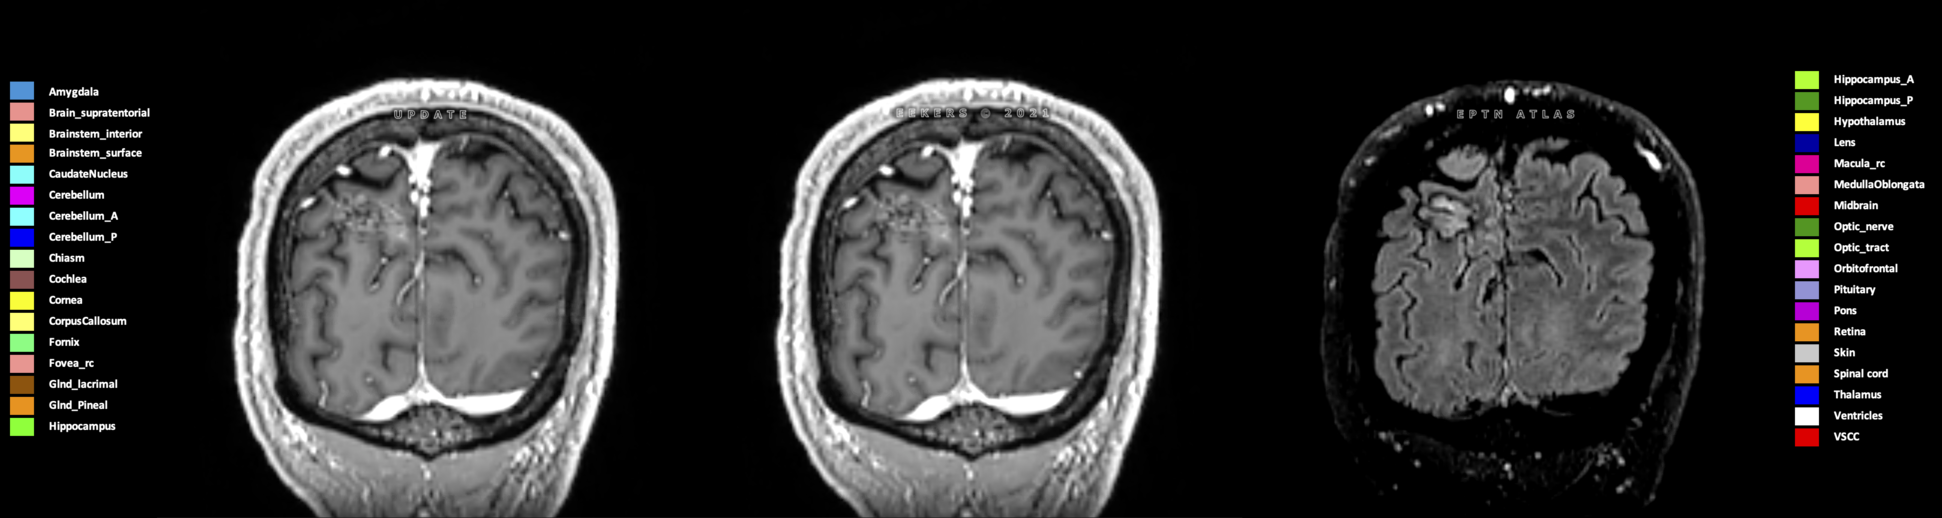

Eekers et al. have published an international neurological atlas for contouring of organs at risk in consensus with the European Particle Therapy Network (EPTN) in 2018 and an update in 2021. The purpose of this consensus atlas is to decrease inter- and intra-observer variability in delineating OARs relevant for neuro-oncology.

Included are all OARs known to be relevant for radiation-induced toxicity in neuro-oncology: brain, brainstem (midbrain, pons, medulla oblongata), chiasm, cerebellum (anterior & posterior), cochlea, cornea, hippocampus (anterior & posterior), hypothalamus, lens, lacrimal gland, optic nerve, pituitary, skin, and vestibular & semicircular canals. To further facilitate research on cognition, vision and radiological changes after irradiation of the brain, potential clinically-relevant OARs are included: amygdala, caudate nucleus, cerebellum (anterior & posterior), corpus callosum, fornix, macula, optic tract, orbitofrontal cortex, periventricular space (PVS), pineal gland, and thalamus.

Three-dimensional delineation of the 25 consensus OARs for neuro-oncology are shown on CT (WW/WL 120/40, 3000/600), 3T MR images, (T1Gd, T2FLAIR 1mm) and 7T MR (MP2RAGE 0.7 mm). All are presented in transversal, sagittal and coronal view.